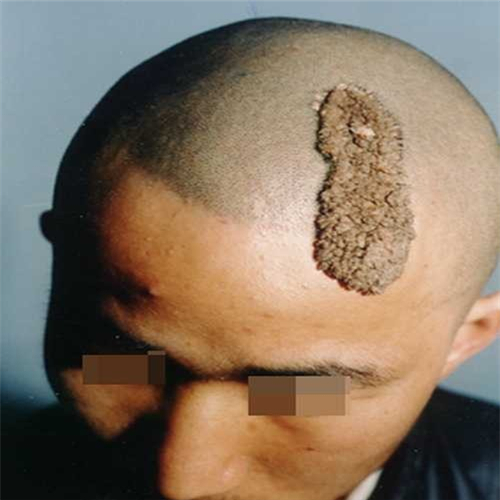

額頭皮脂腺痣

線狀皮脂腺痣

腦後皮脂腺痣切除後

皮脂腺痣手術